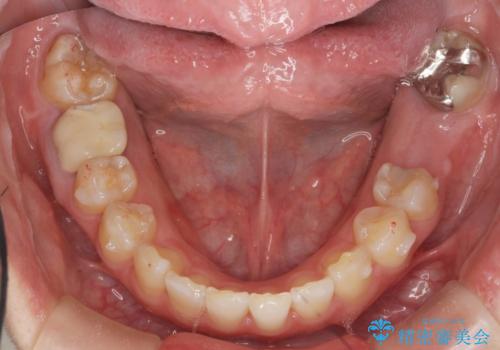

ねじれた前歯を改善するマウスピース矯正

- 大きくねじれた前歯をまっすぐに並べたい。と矯正治療を希望され来院されました。

前歯をきっちり並べるには奥歯の噛み合わせの調整を行い上下の前後的関係を治し、ねじれを取るスペースを確保していきます。

当初前歯だけ治れば良い、という心算で来院されましたが奥歯の噛み合わせも負担が大きく問題の起きやすいことをお伝えし上顎の奥歯をきっちりと後方移動行い噛み合わせの調整を行いました。・